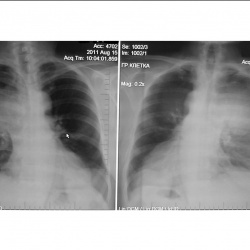

Жалобы на одышку. Архив 6 мес назад без данных изменений. Из анамнеза Са МЖ.Ваши мнения коллеги)

Анамнез Са в/доли правого легкого, в/лобэктомия. Выписан недавно, особо там не возились.Ваши мнения о чем можно думать по рг-картине.